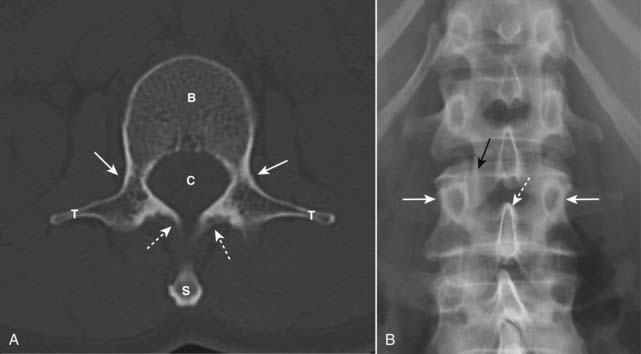

Vertebral Body

image Each vertebra (well, almost every vertebra) has a body composed of inner cancellous bone and marrow and posterior elements made of compact, dense bone consisting of the pedicles, laminae, facets, transverse processes, and a spinous process (Fig. 24-1A).

image In the frontal projection, each vertebral body displays two ovoid pedicles visible on each side of the vertebral body. The pedicles of L5 are frequently difficult to visualize, even in normal individuals due to the lordosis of the lumbar spine (Fig. 24-1B).

image

Figure 24-1 Normal spine, axial CT (A), and frontal conventional radiograph (B).

A, In this CT scan of a “typical” vertebral body, we see the body (B), pedicles (solid white arrows), laminae (dotted white arrows), transverse processes (T), spinal canal (C), and spinous process (S). B, Each vertebral body has two pedicles that project as small ovals on either side of the vertebral body (solid white arrows). The spinous process (dotted white arrow) may be visualized slightly below the body to which it is attached. The facet joint is seen here en face (solid black arrow).